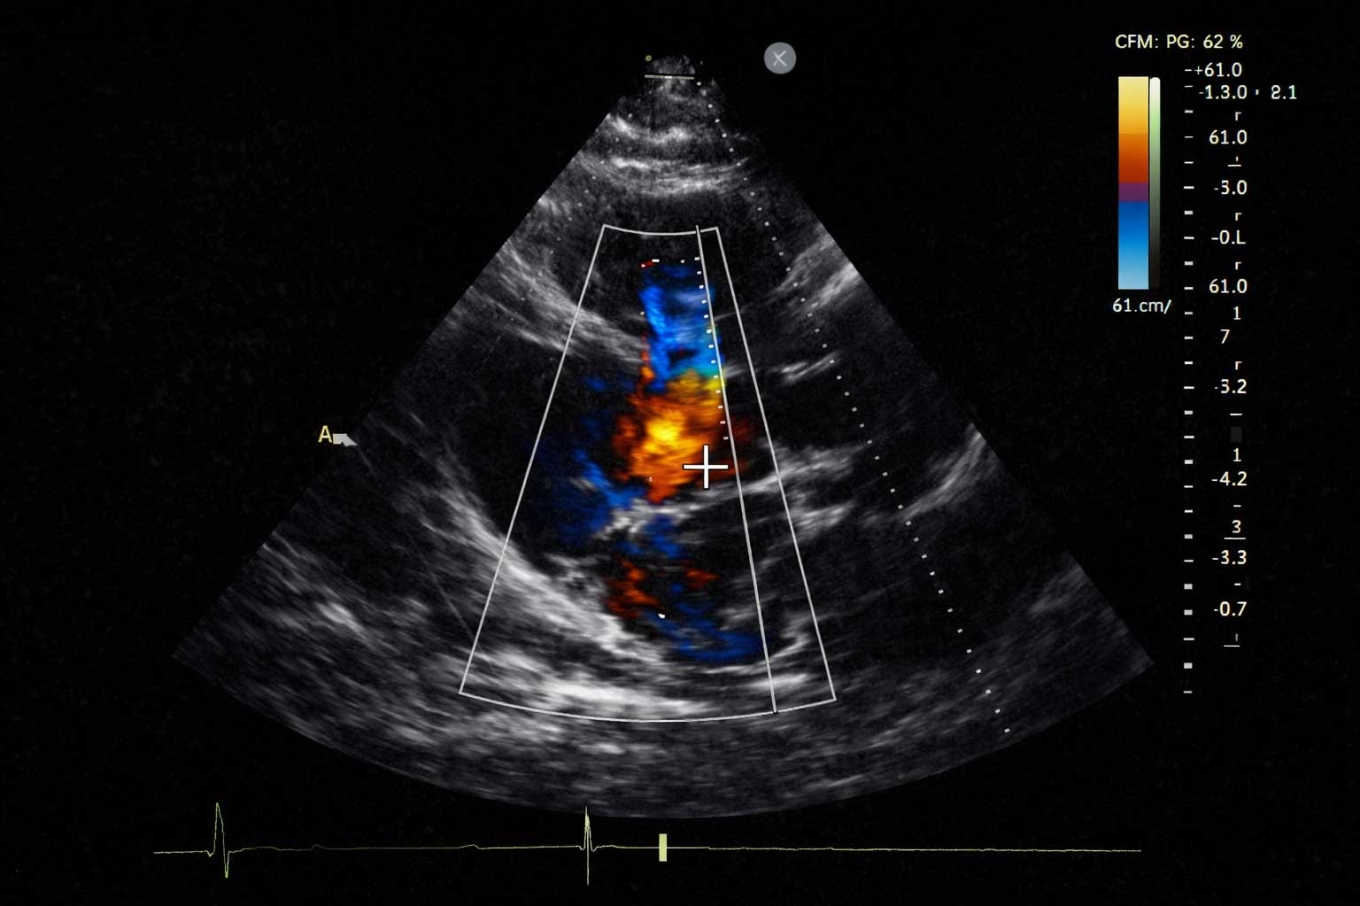

O ecocardiograma é um exame de imagem que utiliza ultrassom para avaliar o funcionamento do coração. Ele permite observar a estrutura cardíaca, o movimento das válvulas e o fluxo de sangue dentro do órgão.

- fluxo sanguíneo dentro das cavidades cardíacas